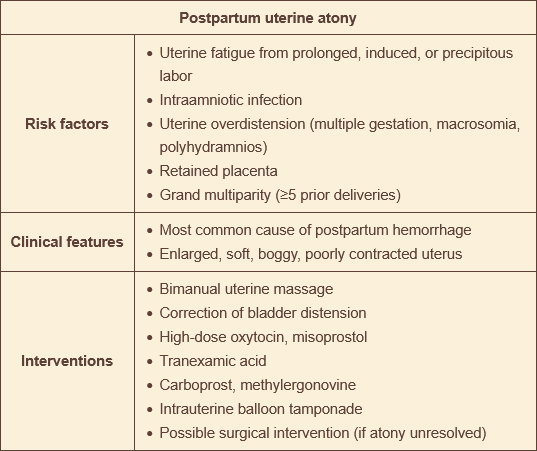

pt has postpartum uterine atony. htn. what do you avoid?

methylergonovine → potent vasoconstrictor → increased risk of stroke in hypertensive pts

how to treat postpartum uterine atony

bimanual uterine massafe & high-dose oxytocin

tranexamic acid - antifibrinolutic (best within 3 hrs of delivery, use for any PPH like retained placenta)

carboprost tromethamine - stimulates contractions to increase tone & decrease bleeding; synthetic prostaglandin f2a analog, CAN CAUSE BRONCHOSPASM

methylergonovine - potent vasoconstrictor